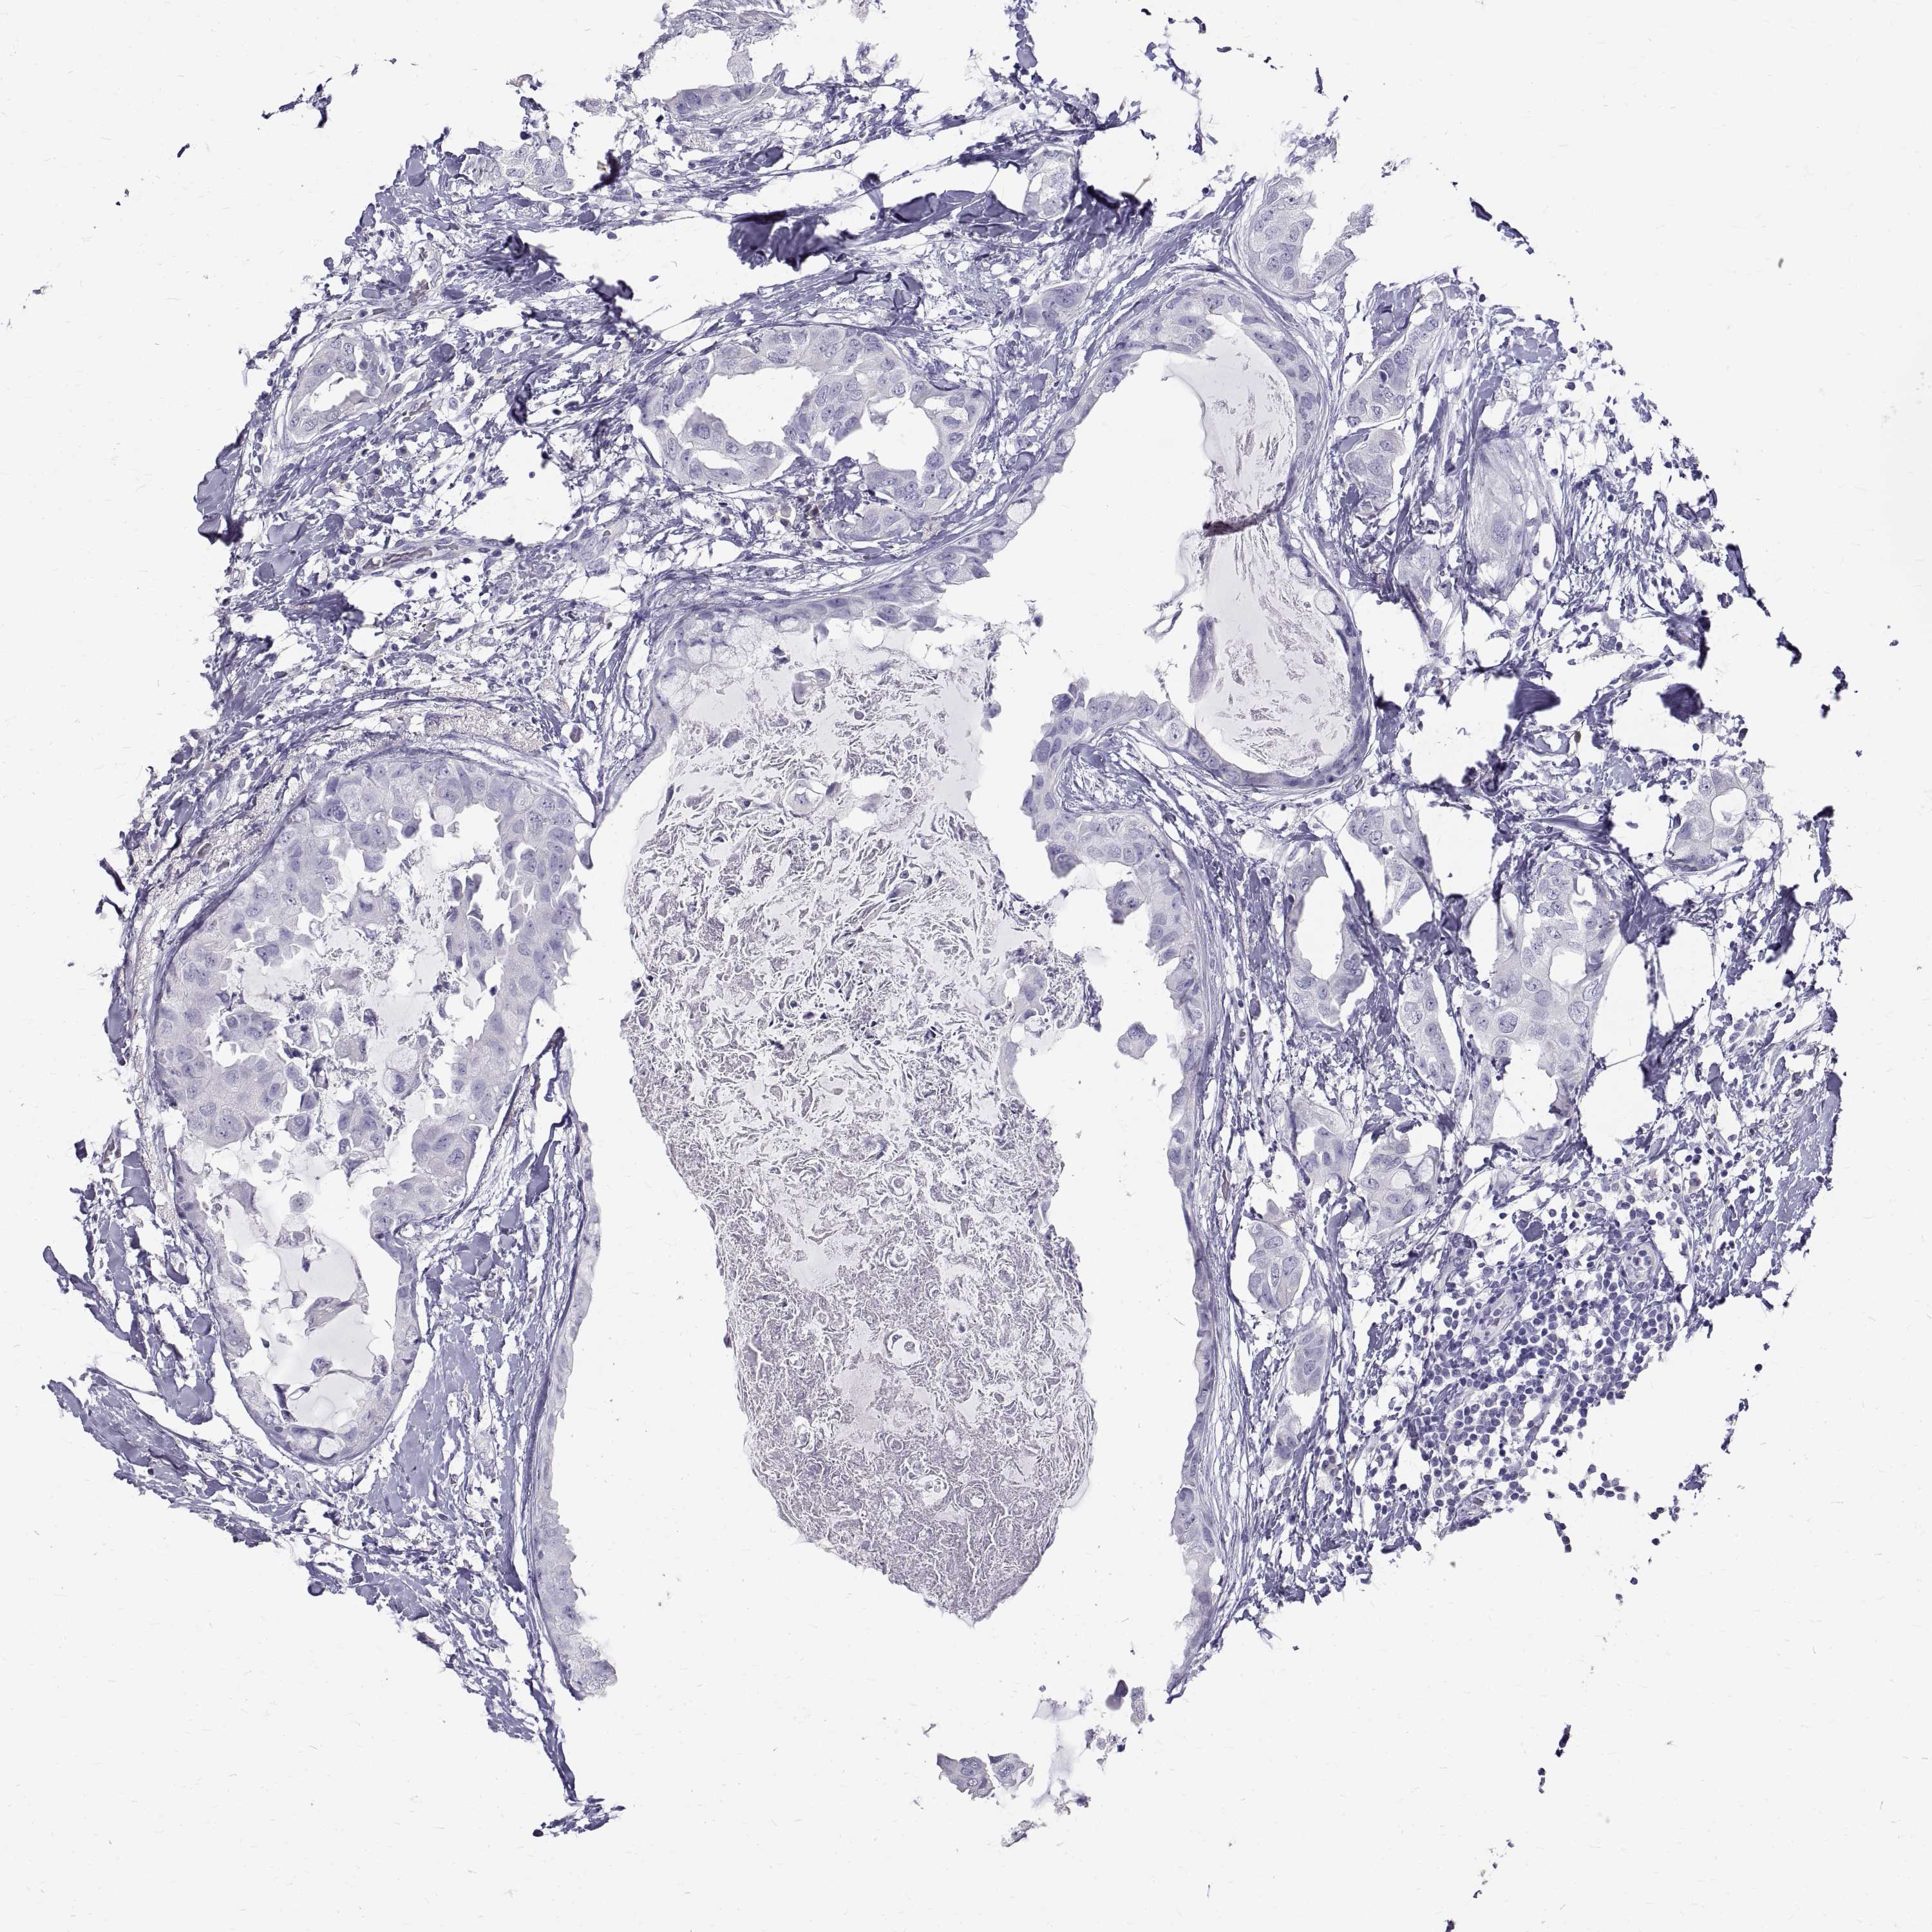

BRCA TCGA BRCA VALIDATION PROTEIN EXPRESSION

Breast cancer

Human cancer